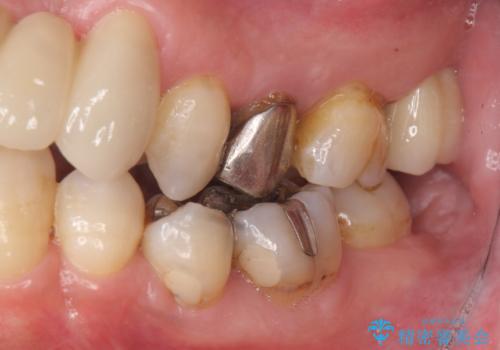

- 歯周病を気にして来院。

前歯の虫歯を治そうにも、歯並びの問題で難しい状態でした。

右下の奥歯も欠損しており、インプラント治療が必要な状態でした。

前歯が重なっているところの虫歯治療が難しく、そこから矯正治療の提案となりました。

下の前歯1本、また、左上2番を保存不可能なため抜歯しています。